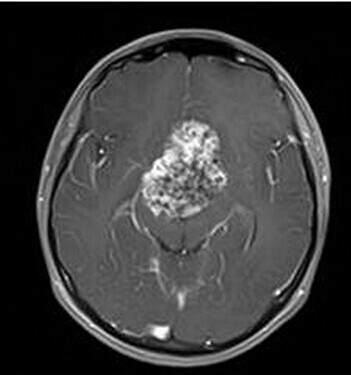

患者:男,15岁,双眼视力下降1年余,近来有嗜睡表现。

【正确答案】A 颅咽管瘤

(1)颅咽管瘤的两个发病高峰年龄分别是4-15岁和35-45岁,其中实性颅咽管瘤多见于成年人,本例为青少年患者,发病年龄无特异性;

(2)对诊断有提示意义的征象是明显强化,内散在微囊状不强化区。